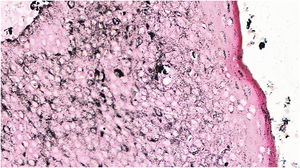

The histopathological examination revealed a well-defined nodular neoplasm, connected with the epidermis, consisting of small, monomorphic, cuboidal cells, with ample, eosinophilic cytoplasm and well-defined borders, in addition to conspicuous intercellular Bridges. There were melanin deposits diffusely distributed inside the neoplasm. Moreover, intracytoplasmic lumens and ductular formations delineated by cuticles (Figs. 2‒4) were observed in some tumor cuboidal cells. The tumor lobules did not show stromal retraction or peripheral nuclear palisading.

Pigmented eccrine poroma (Hematoxylin & eosin, ×100). Neoplasm consisting of small cuboidal cells with ample cytoplasm (smaller than the keratinocytes), with melanin deposition diffusely distributed within the neoplasm. The neoplasm is connected to the epidermis but there is no peripheral palisading.